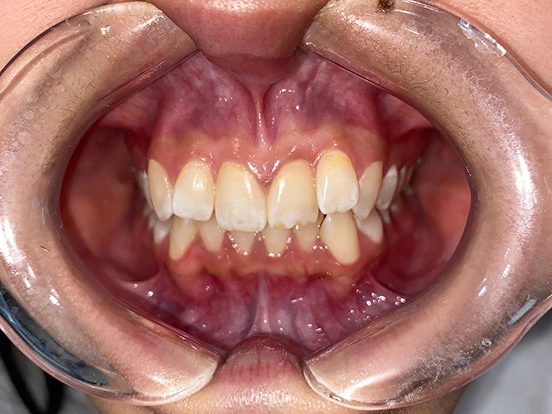

Invisalign CK

This Invisalign case shows how clear aligners can completely transform a smile without the need for metal braces. Over the course of treatment, CK achieved a beautifully aligned smile with improved symmetry and confidence. The results highlight how Invisalign offers both comfort and precision for a stunning new look.